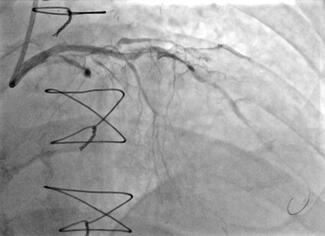

The authors present the case of a patient who was admitted for a non-ST-elevation myocardial infarction caused by an left ventricular outflow tract pseudoaneurysm, resulting in coronary systolic compression.